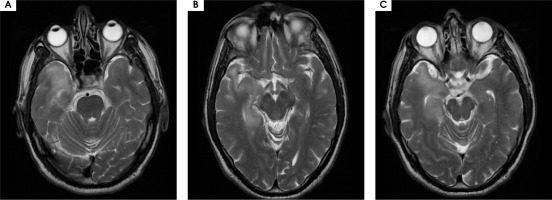

A 48-year-old male patient was admitted to the outpatient neurological clinic with complaints of numbness on the left side of his face, instability, spasms in all four extremities lasting for about 45 seconds, insomnia, and excessive talkativeness. In neurological examination, his general condition was good, he was conscious but showed psychomotor agitation, with difficulty concentrating and excessive talkativeness. He had dysarthria; his muscle strength and gait were normal. Sensory examination was normal, cerebellar examination was normal. Deep tendon reflexes (DTR) were normoactive in both upper and lower extremities, plantar response was flexor. There was no sign of meningeal irritation. In brain magnetic resonance imaging (MRI), an iso-hyperintense appearance was recorded in the hippocampus trace in the medial part of the right temporal lobe, and in the hyperintense ADC map in DWI. At this level, hyperintense cortical-subcortical and periventricular signal changes are accompanied on T2 images. Faint sulcal-like enhancements were observed. MRI findings were evaluated in favor of encephalitis (Figure I).

Figure I

Hyperintense signal changes in the right temporal lobe hippocampal region on brain MRI T2 sequence